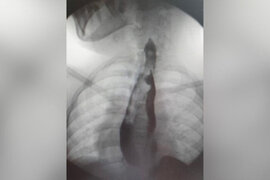

İki mədəsi olan qız əməliyyat olundu

Rusiya Uşaq Klinik Xəstəxanasının cərrahları qarnı və yemək borusu qoşa olan Yakutiyadan olan məktəbli qızı əməliyyat ediblər. bildirir ki, 14 yaşlı məktəbli qız qarın nahiyəsində vaxtaşırı ağrılardan şikayətləndiyi üçün ailə yaşadıqları yer üzrə klinikaya müraciət edib. Müayinə zamanı nadir bir patoloj

10 noyabr 2023